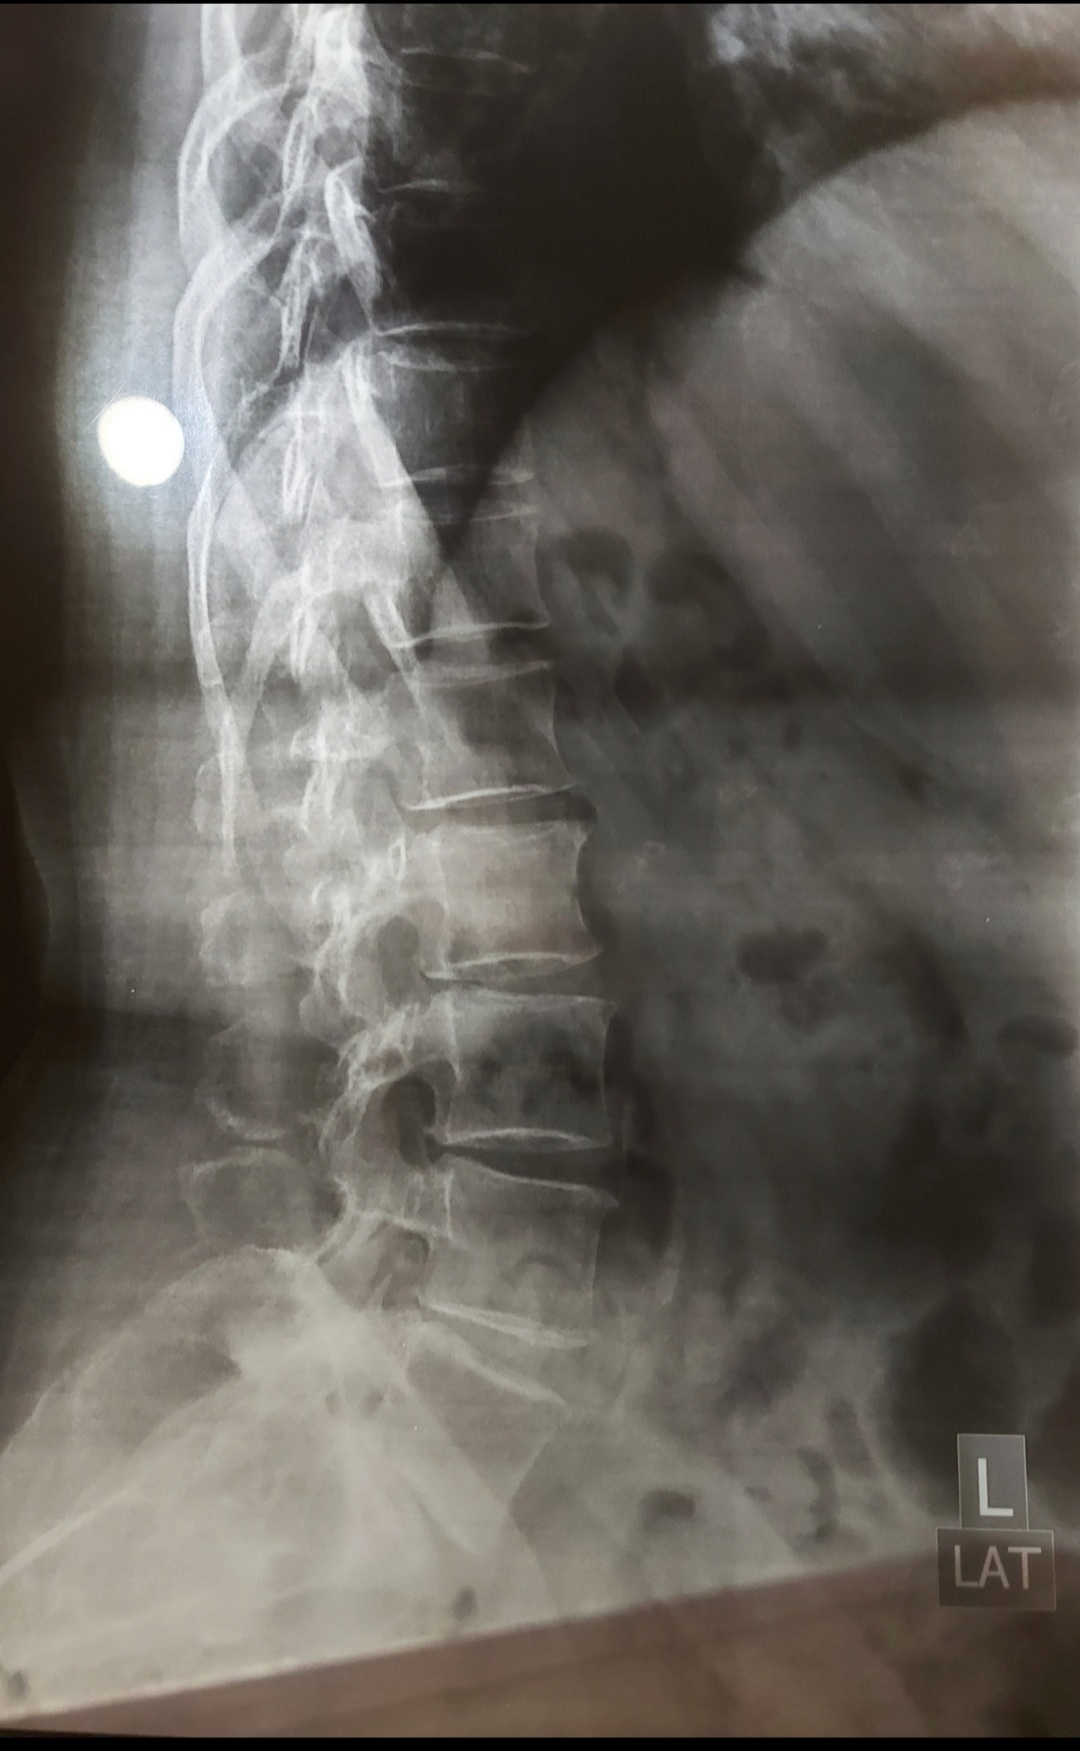

I have pain in my tail bone. Now I have when I sit or stand or lay on bed. Doc said its inflammation HISTORY--> tailbone was injured by falling 2 times at the same spot 5 years ago. I had that similar pain always while sitting or standing for long time but now it has increased n its very painful cant sit in my class. XRAY ATTACHED Thank you in advance